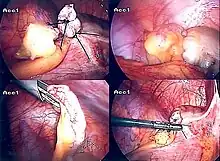

Inflamed appendix removal by open surgery

Laparoscopic appendectomy.

The surgical procedure for the removal of the appendix is called an appendectomy. Appendectomy can be performed through open or laparoscopic surgery. Laparoscopic appendectomy has several advantages over open appendectomy as an intervention for acute appendicitis.[72]

Laparoscopic appendectomy

Laparoscopic appendectomy has become an increasingly prevalent intervention for acute appendicitis since its introduction in 1983.[76] This surgical procedure consists of making three to four incisions in the abdomen, each 0.25 to 0.5 inches (6.4 to 12.7 mm) long. This type of appendectomy is made by inserting a special surgical tool called a laparoscope into one of the incisions. The laparoscope is connected to a monitor outside the person's body, and it is designed to help the surgeon to inspect the infected area in the abdomen. The other two incisions are made for the specific removal of the appendix by using surgical instruments. Laparoscopic surgery requires general anesthesia, and it can last up to two hours. Laparoscopic appendectomy has several advantages over open appendectomy, including a shorter post-operative recovery, less post-operative pain, and lower superficial surgical site infection rate. However, the occurrence of an intra-abdominal abscess is almost three times more prevalent in laparoscopic appendectomy than open appendectomy.[77]